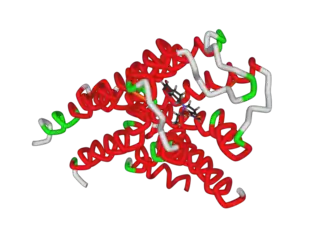

Rotigotine acts as a non-selective agonist of the dopamine D1, D2, D3, and, to a lesser extent, D4 and D5 receptors, with highest affinity for the D3 receptor.[9] In terms of affinity, rotigotine has 10-fold selectivity for the D3 receptor over the D2, D4, and D5 receptors and 100-fold selectivity for the D3 receptor over the D1 receptor.[9] In functional studies however, rotigotine behaves as a full agonist of D1, D2, and D3 with similar potencies (EC50).[9] Its ability to activate both D1-like and D2-like receptors is similar to the case of apomorphine (which notably has greater efficacy in the treatment of Parkinson's disease than D2-like-selective agonists but has suboptimal pharmacokinetic properties) and pergolide but unlike pramipexole and ropinirole.[9]

All affinities listed were assayed using human materials except that for α2B-adrenergic which was done with NG 108–15 cells. Rotigotine behaves as a partial or full agonist (depending on the assay) at all dopamine receptors listed, as an antagonist at the α2B-adrenergic receptor, and as a partial agonist at the 5-HT1A receptor.[10] Though it has affinity for a large number of sites as shown above, at clinical doses rotigotine behaves mostly as a selective D1-like (D1, D5) and D2-like (D2, D3, D4) receptor agonist, with its α2B-adrenergic and 5-HT1A activity also possibly having some minor relevance.